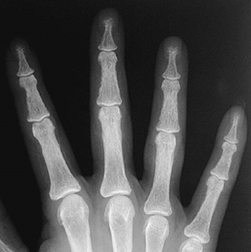

Fig 44 B. Hiperparatiroidismo.

Rx AP. Aumento de la densidad ósea, en un paciente con hiperparatiroidismo.